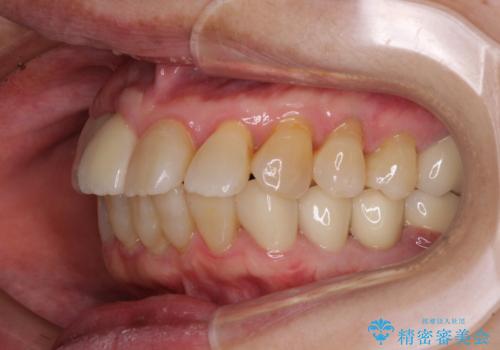

- 歯の欠損や歯肉からの出血などを気にして来院された患者様です。

診査の結果、歯周病であることが分かり、抜歯が必要な歯も見受けられました。

骨造成やインプラント、歯周外科、歯肉移植、矯正など、多くの処置を組み合わせて治療を行うこととしました。

数多くの外科処置を行ったため、治療期間は長期間となりました。

一方、外科処置をしっかりと行ったことで、歯周病の状態は改善され、安定した状態にしあげることができました。